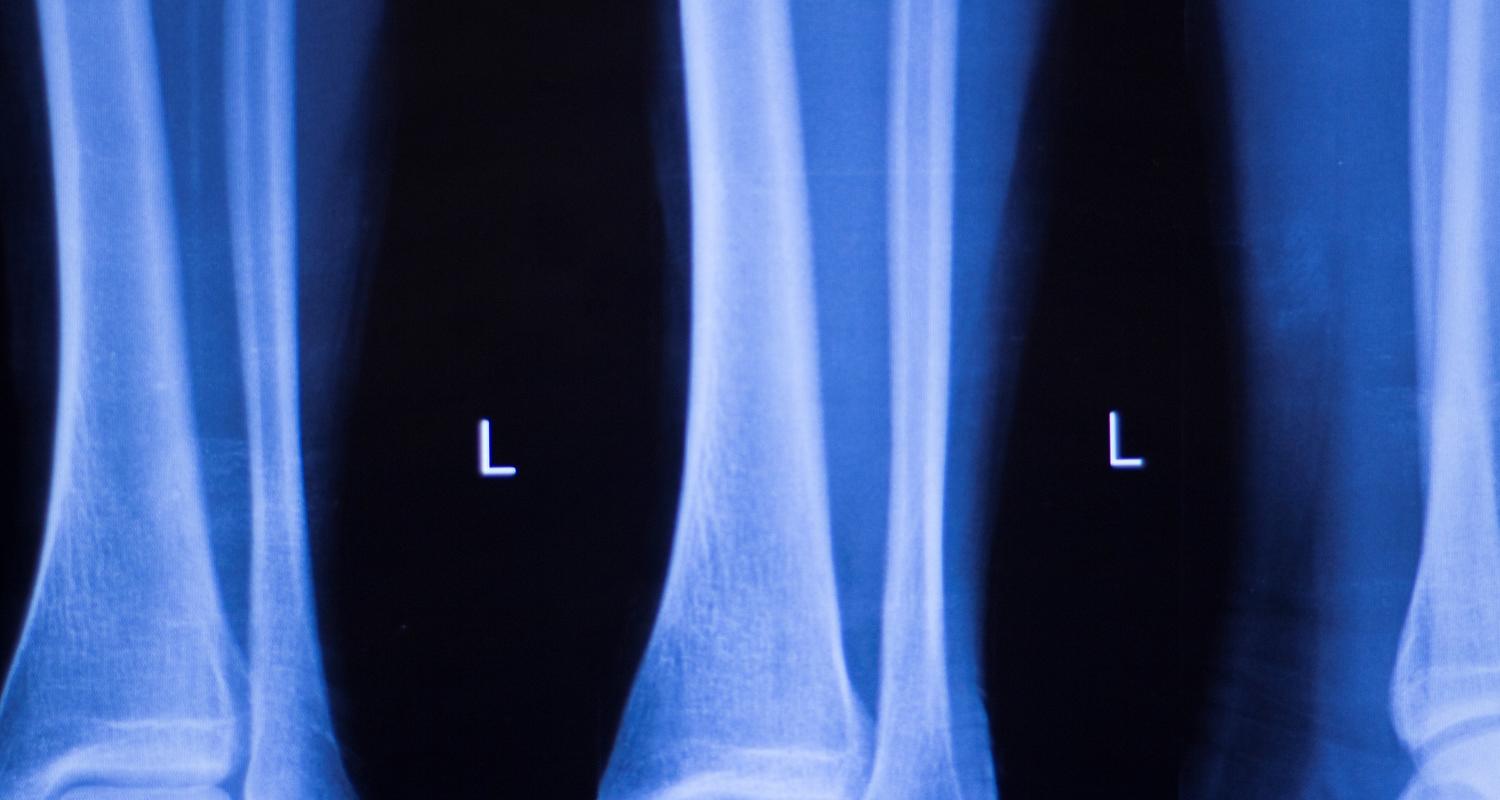

Tibial Stress Fracture Study

Researchers are looking for participants for a study using 3D motion capture and advanced medical imaging to assess how tibial stress fracture risk is altered while walking and running with body-borne loads (up to 50 lb).